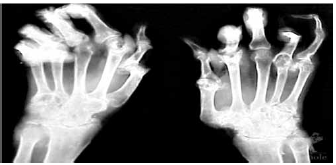

Reumatologia

O RX seguinte sugere

gota.

artrite séptica.

artrite reumatoide.

lúpus eritematoso sistêmico.

febre reumática.